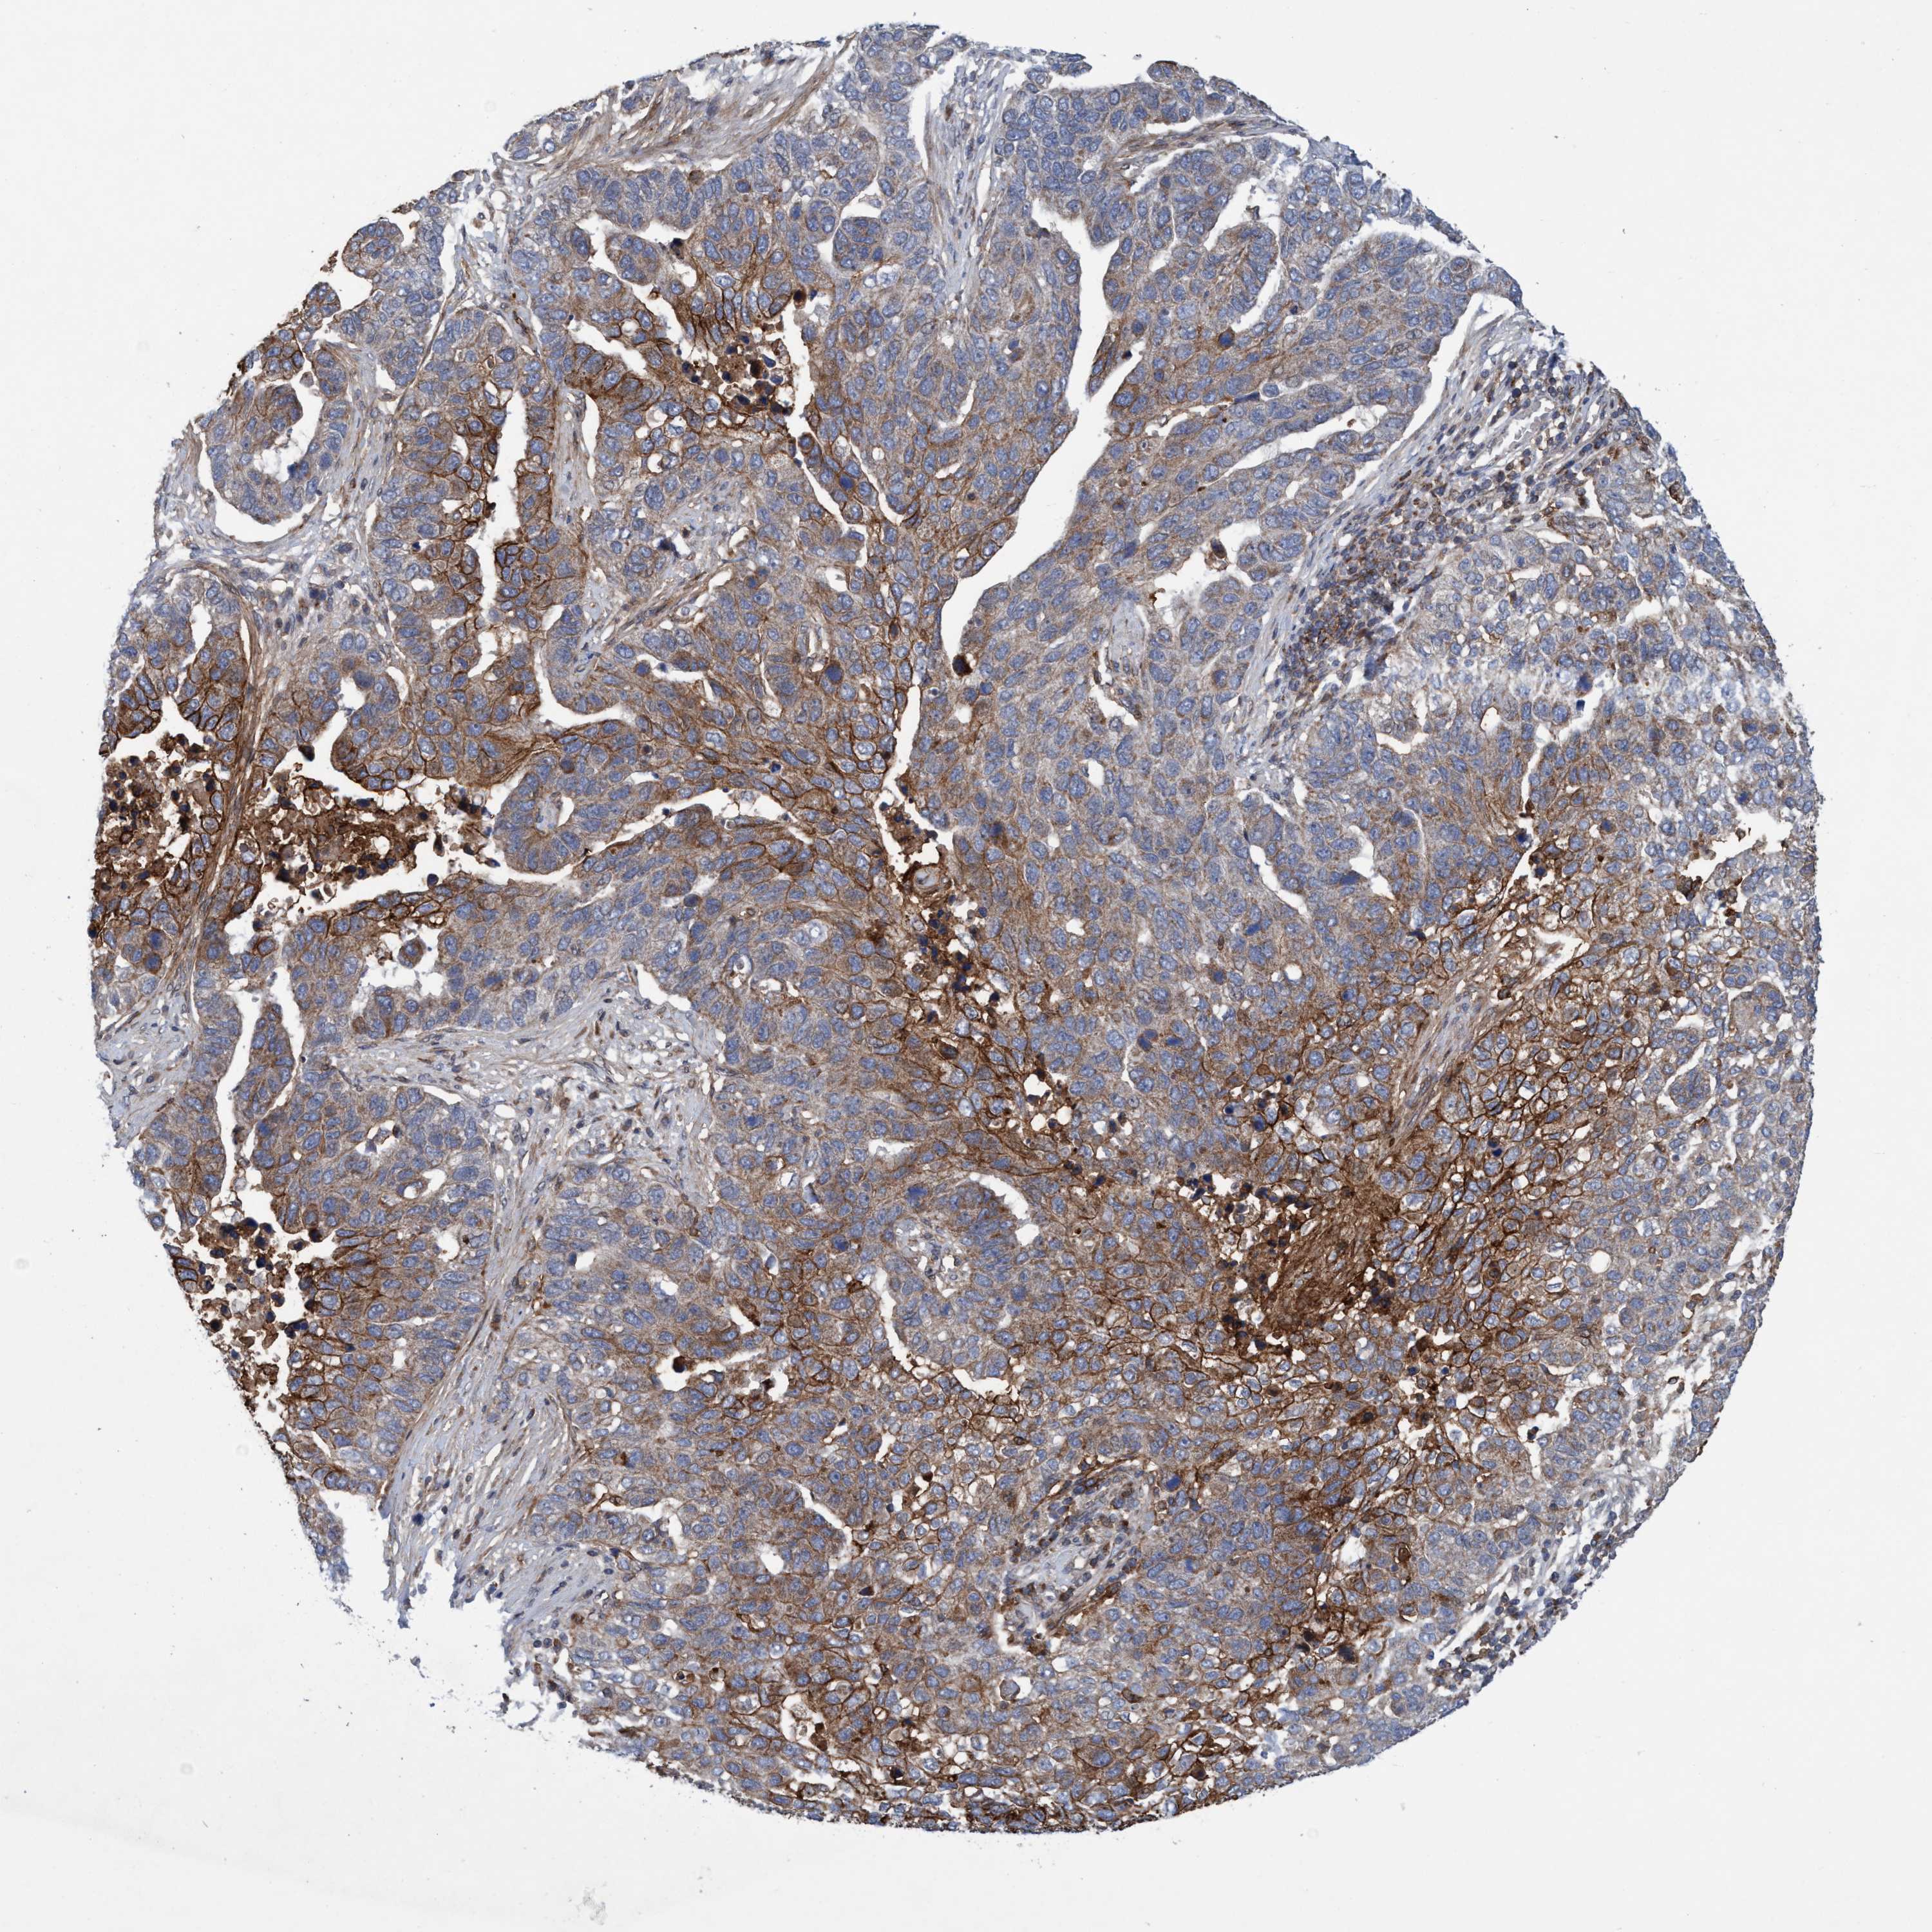

PANCREATIC CANCER - Protein expressioni

A mouse-over function shows sample information and annotation data. Click on an image to view it in a full screen mode. Samples can be filtered based on level of antibody staining by selecting one or several of the following categories: high, medium, low and not detected. The assay and annotation is described here.

Note that samples used for immunohistochemistry by the Human Protein Atlas do not correspond to samples in the TCGA dataset.

Antibody stainingi

Antibody staining in the annotated cell types in the current human tissue is reported as not detected, low, medium, or high, based on conventional immunohistochemistry profiling in selected tissues. This score is based on the combination of the staining intensity and fraction of stained cells.

Each image is clickable and will lead to virtual microscopy that enables deeper exploration of all samples and also displays staining intensity scores, fraction scores and subcellular localization as well as patient and tissue information for each sample.

Antibody HPA021451

Antibody CAB017490

Staining

High

Medium

Low

Not detected

Intensity

Strong

Moderate

Weak

Negative

Quantity

>75%

75%-25%

<25%

None

Location

Nuclear

Cytoplasmic/membranous

Cytoplasmic/membranous,nuclear

Adenocarcinoma, NOS